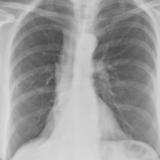

RLL Collapse  1 Lateral

Date: 02/28/2004

Views: 3258